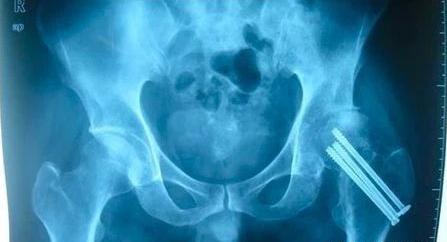

1.股骨颈骨折后没有得到及时的处理,缺血性坏死的发生率也随之增加。早期手术干预,可一定程度降低坏死几率,推迟坏死时间,并减少坏死区域。

2.骨折处越靠近股骨头,其坏死率也越高。

3.股骨颈骨折原始移位严重,股骨头血管可能受到严重损害,股骨头坏死发生率也较高。

4.骨折后复位不良,如过度内收、屈曲或外翻旋转和分离移位等手法,均可增加坏死率,

勤查X线片:股骨颈骨折患者要定期检查,复查X线片,即使骨折愈合,也要追踪3-5年。